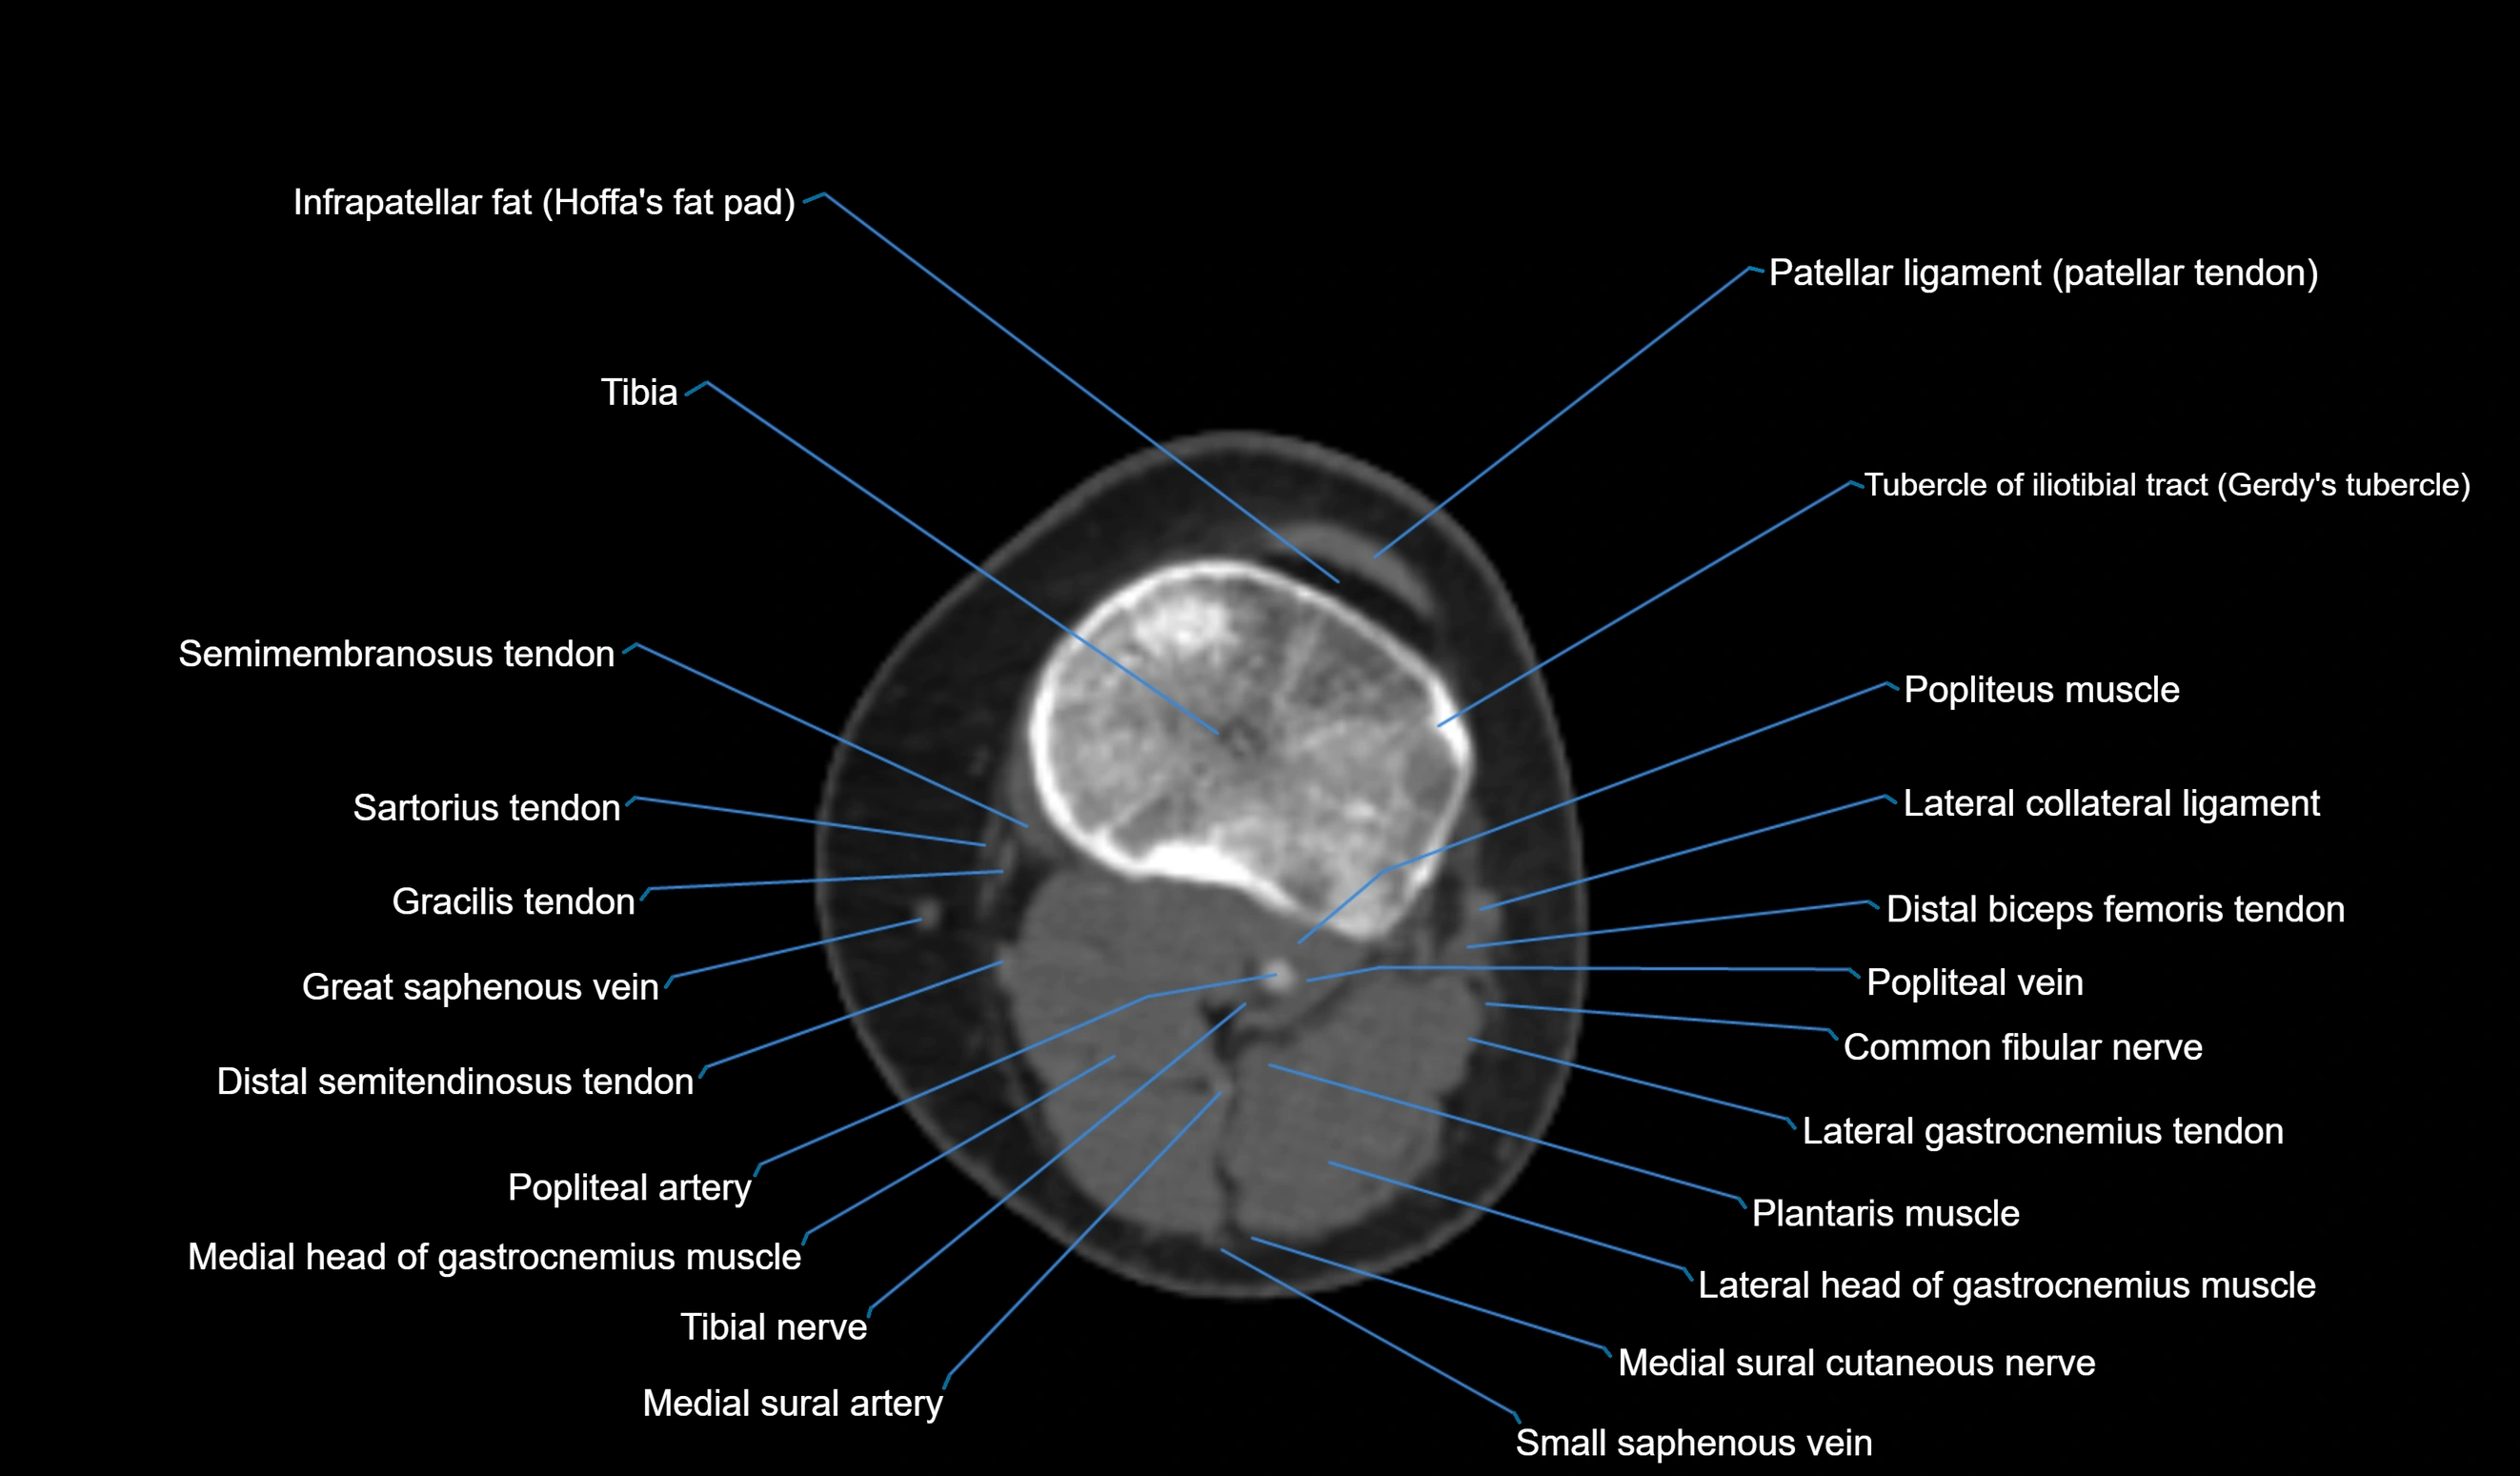

CT VRT 3D image

CT image